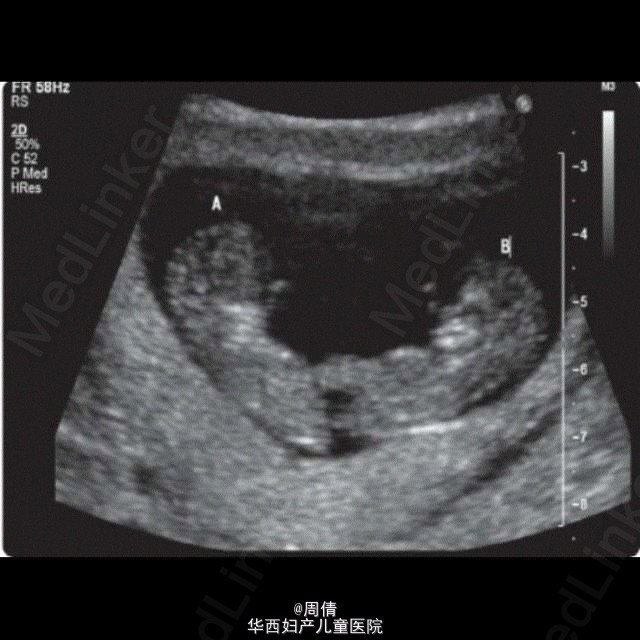

超声诊断单绒毛膜双胎羊膜囊融合一例

37岁女性,G3P1,自然受孕9w。 阴道超声示:子宫腔单个妊娠囊内2个胎儿,单绒毛膜。拥有共同的卵黄囊,在脐周相互连接。